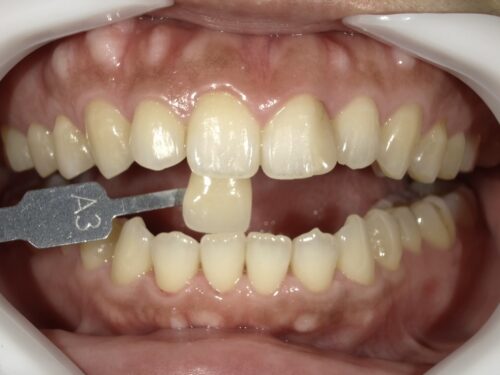

ドイツのVITA社のシェードガイドという色見本を用いて、この患者さんの歯の色を確認します。

A3という日本人の標準的な色合いであることがわかりました。